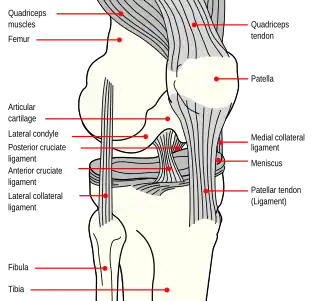

In human anatomy, the quadriceps tendon works with the quadriceps muscle to extend the leg. All four parts of the quadriceps muscle attach to the shin via the patella (knee cap), where the quadriceps tendon becomes the patellar ligament. It attaches the quadriceps to the top of the patella, which in turn is connected to the shin from its bottom by the patellar ligament. A tendon connects muscle to bone, while a ligament connects bone to bone.[1]